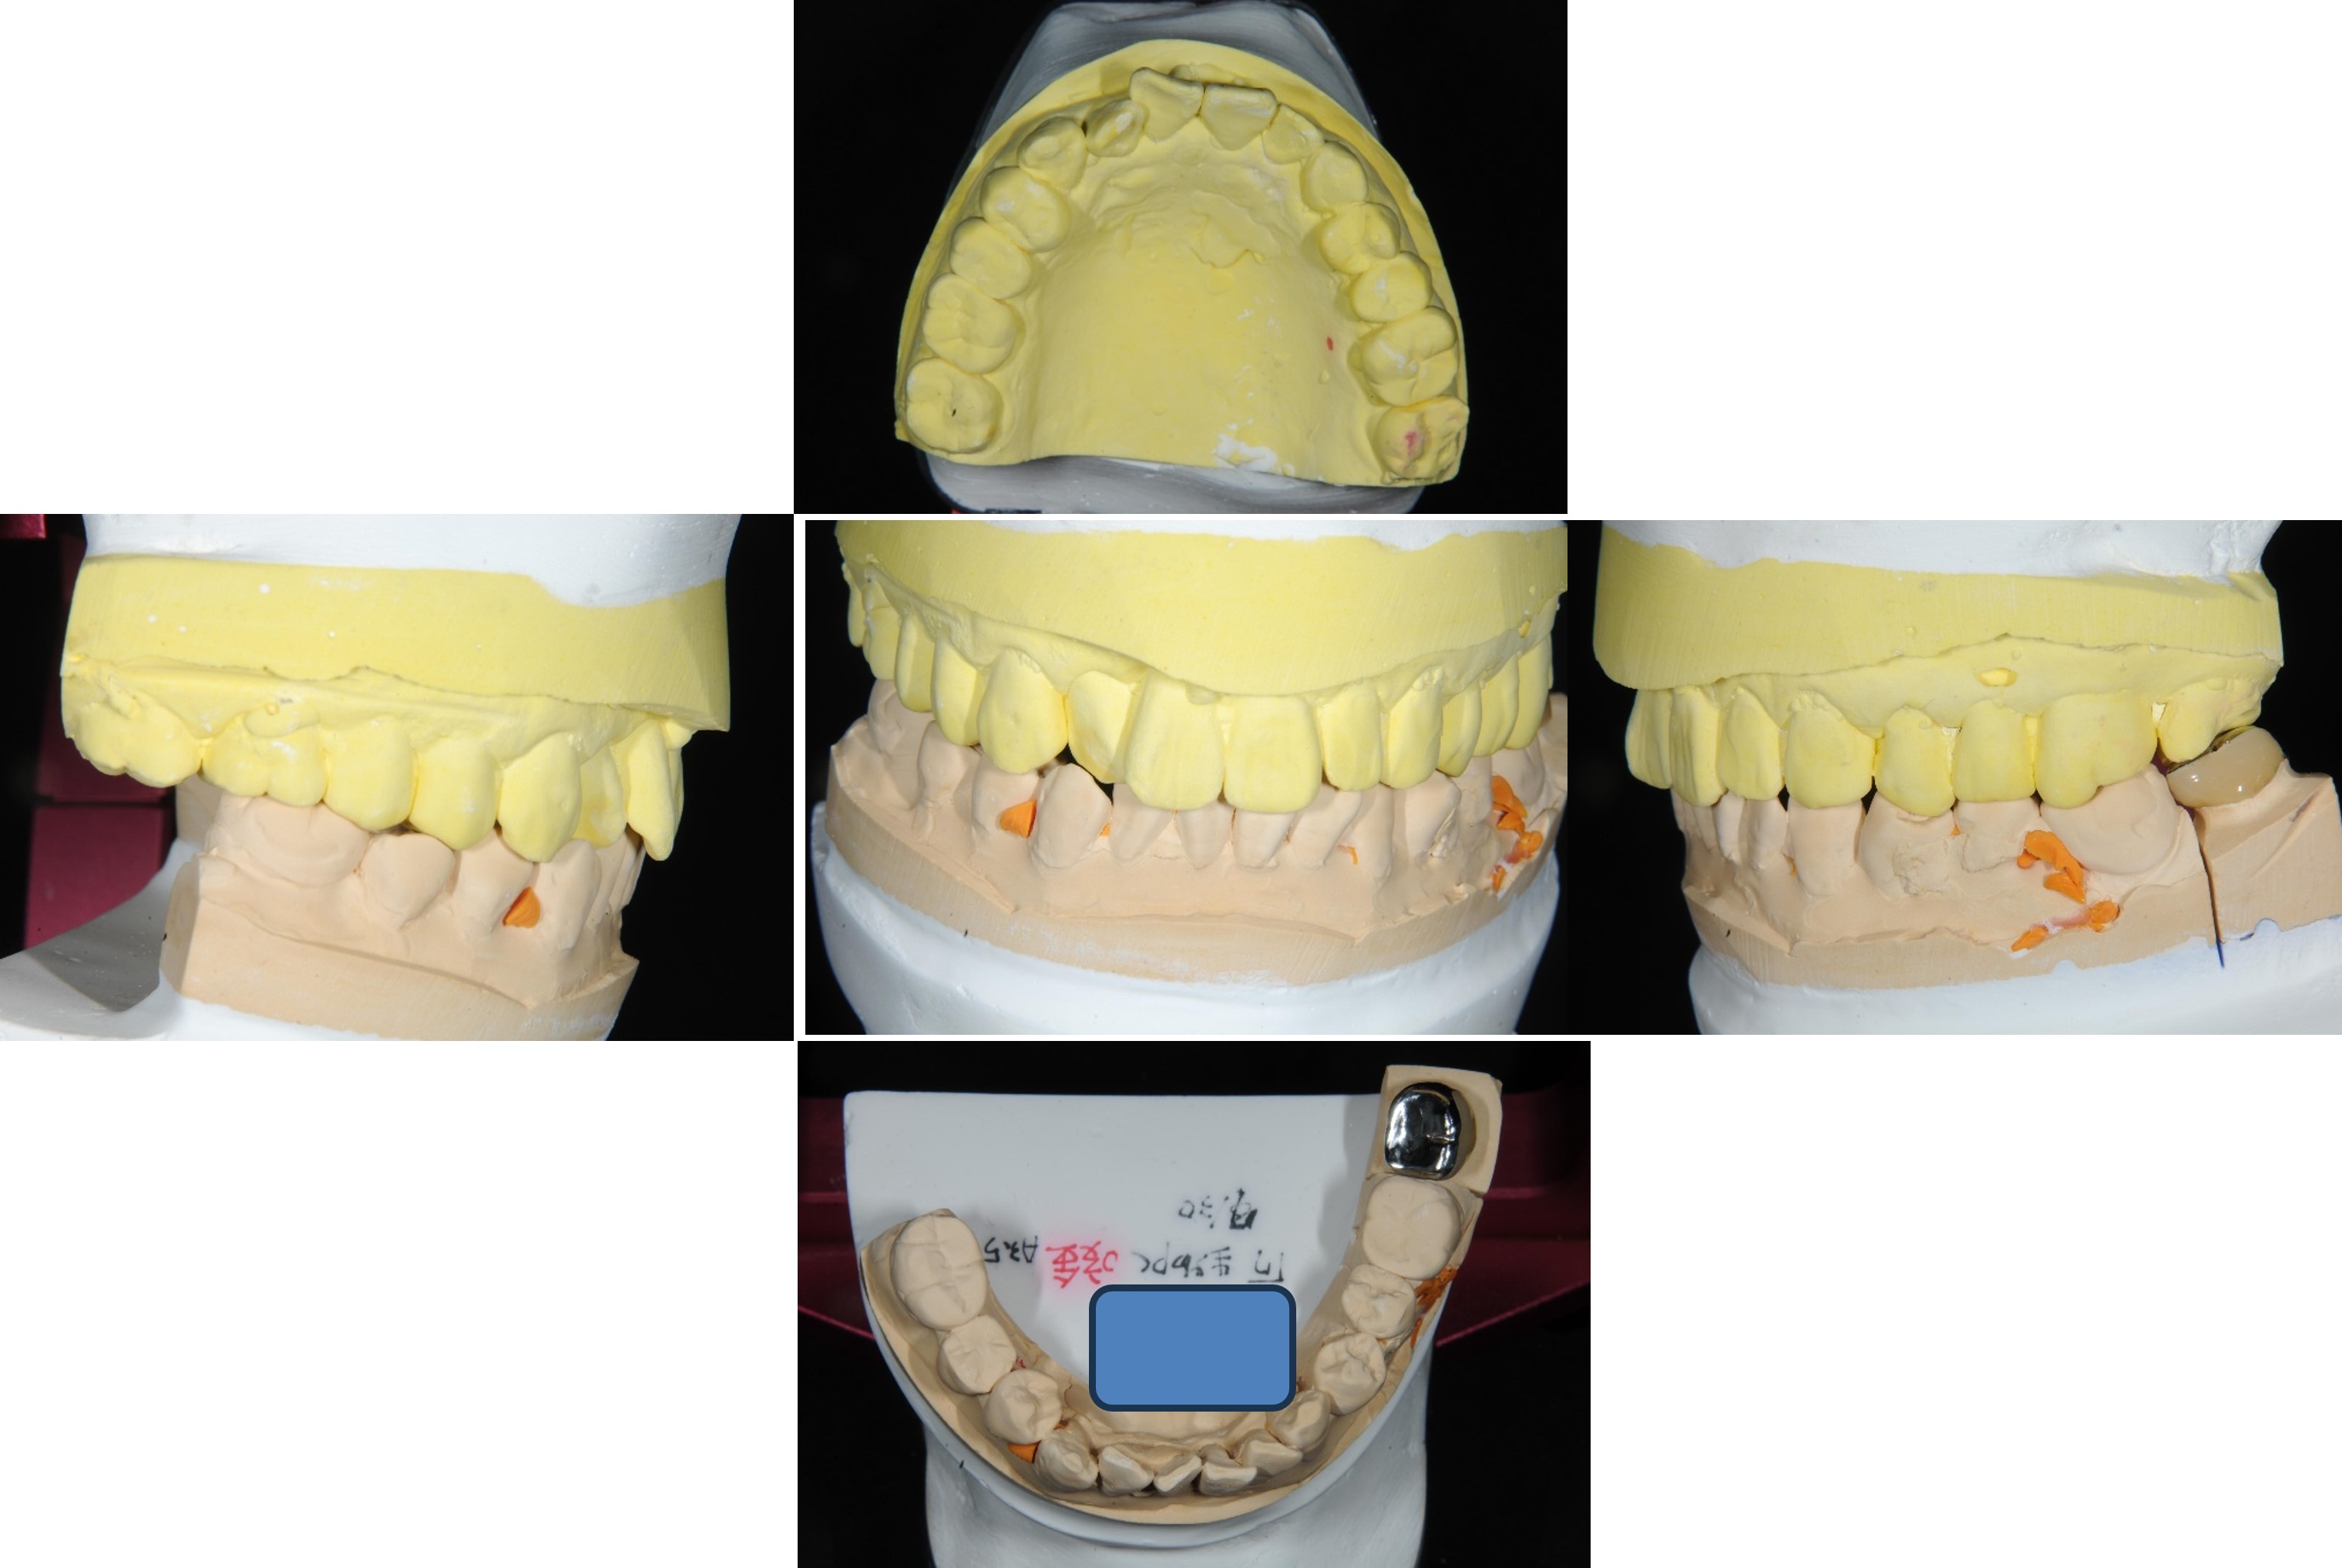

於半調節咬合器製作假牙

咬合器製作假牙